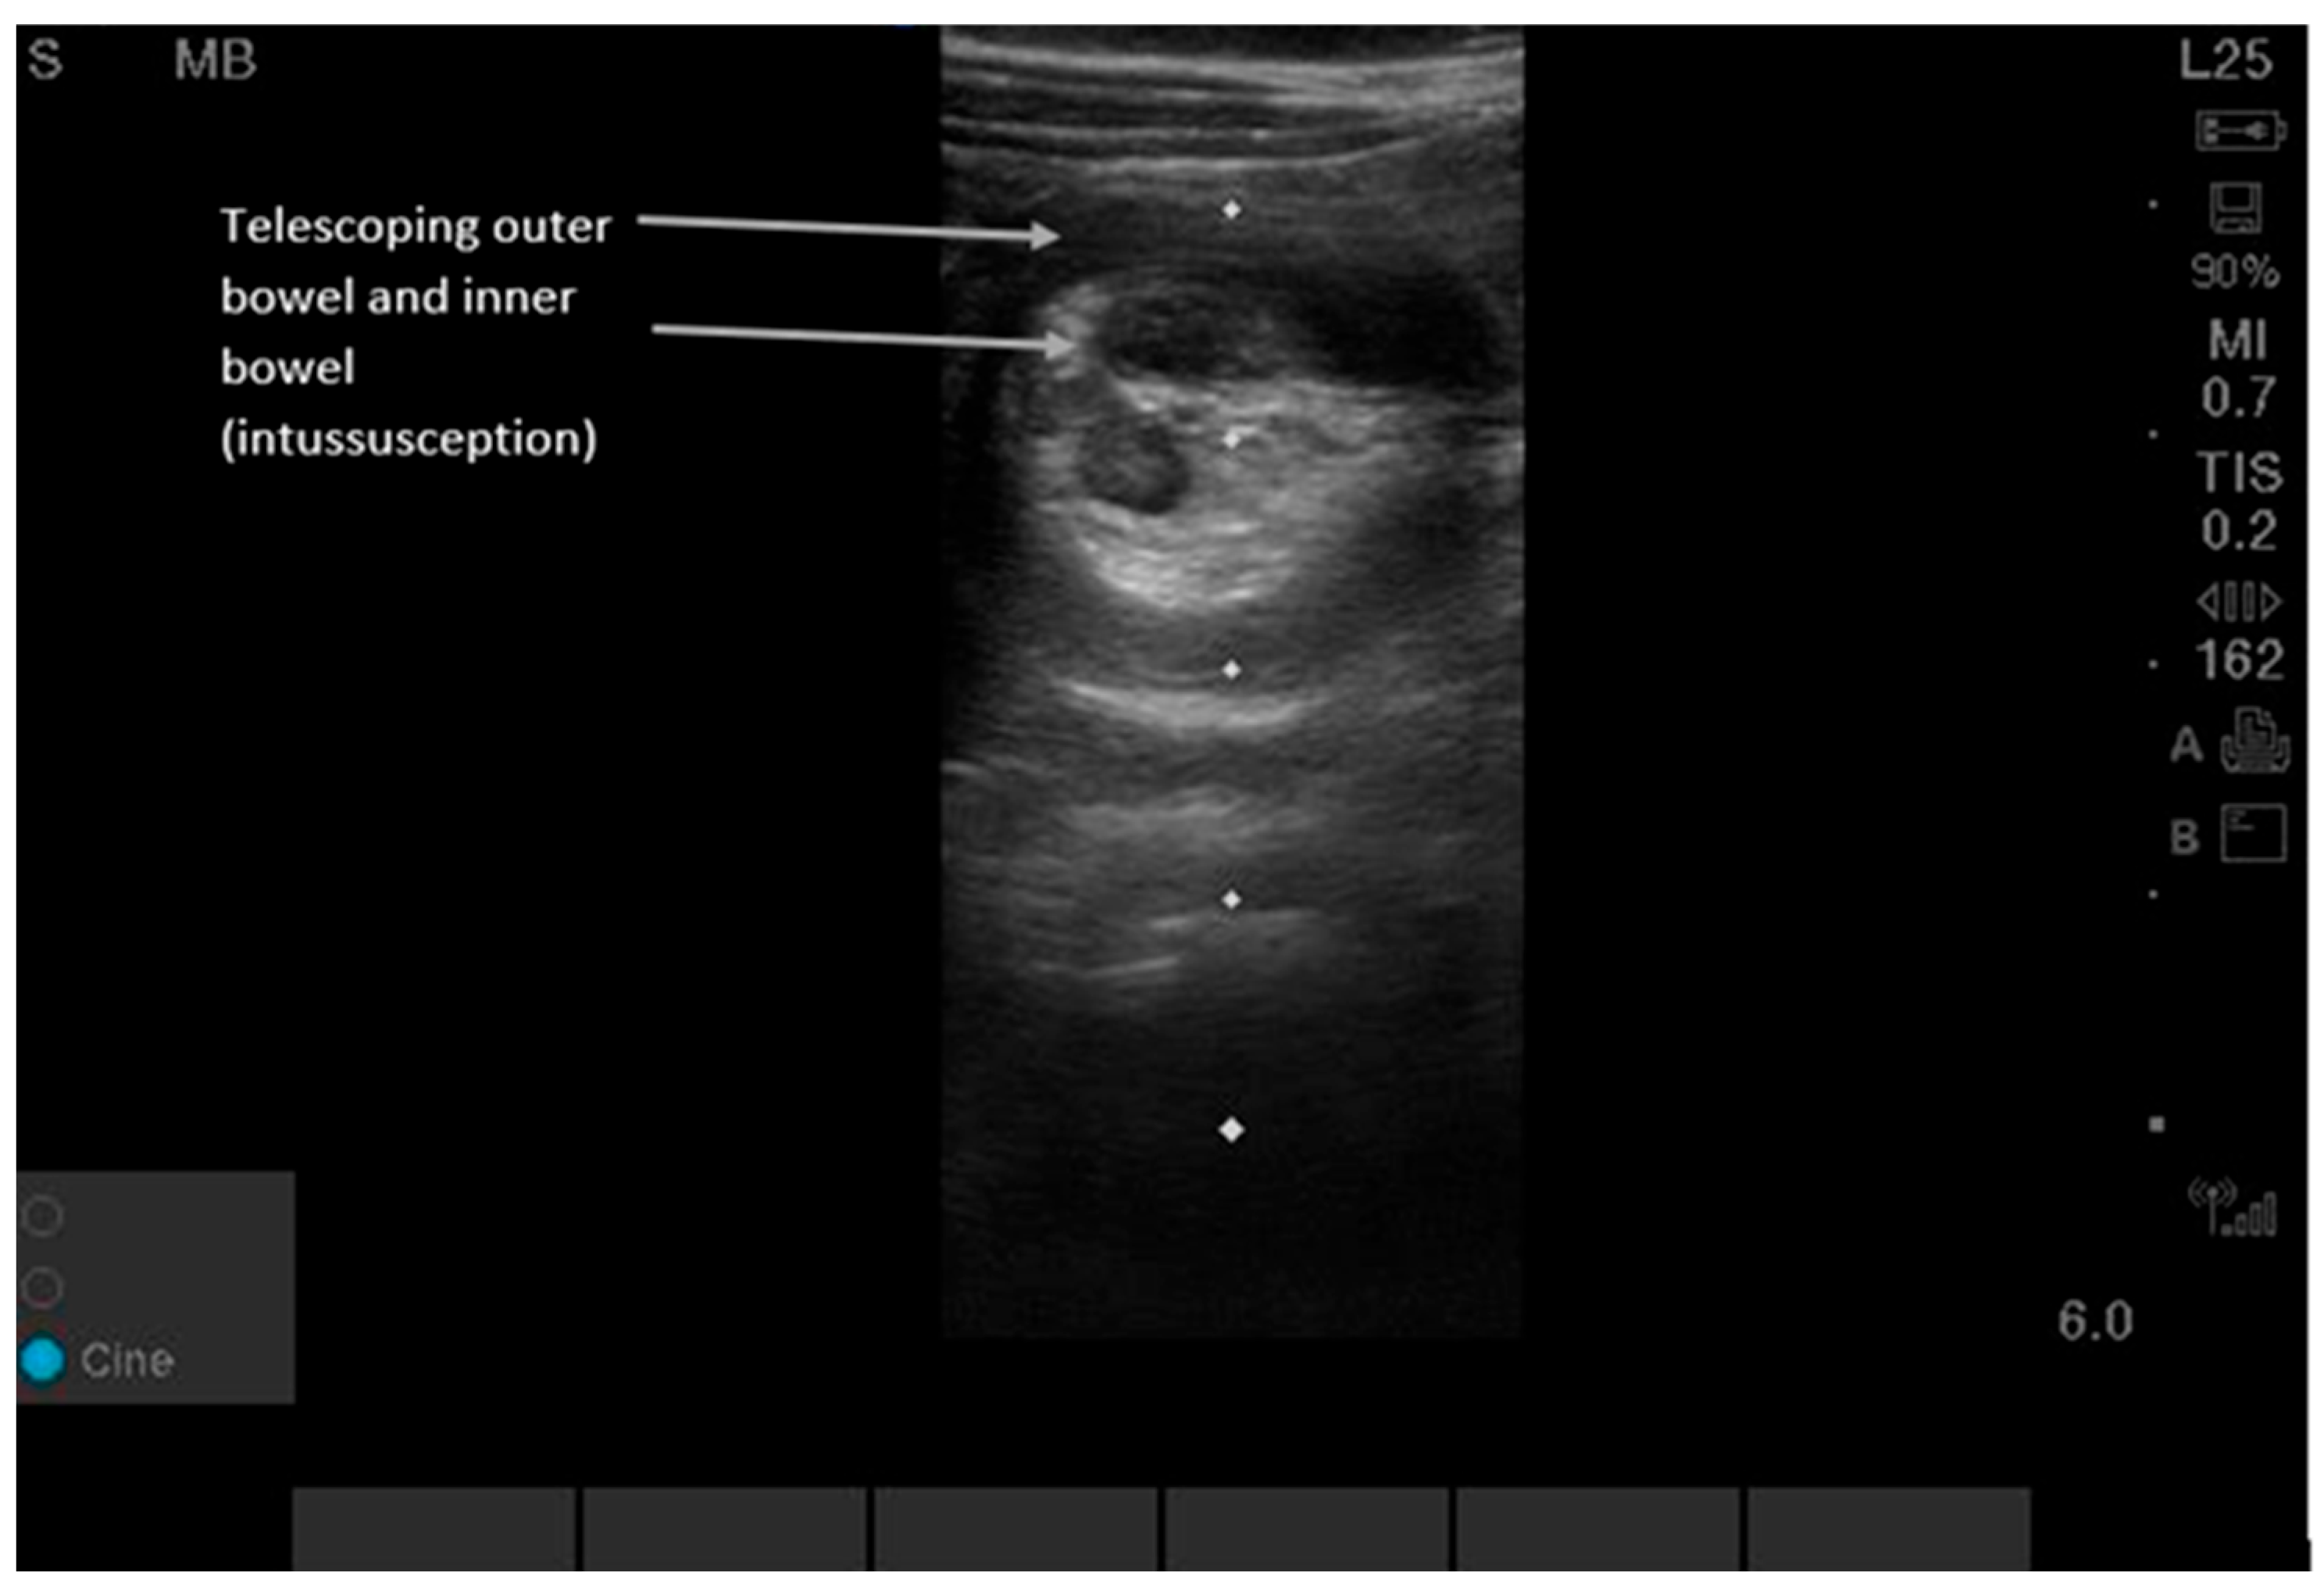

Intussusception can be detected by either the lawnmower or the point-of-maximal-pain technique. Users can begin in the right upper quadrant since this is the most common location (80% of intussusceptions are ileo-colonic) and then scan along the entire colon in the peripheral abdominal wall area using a “picture-frame” technique [23,24,25,26]. Supplementary Video S5 shows dynamic findings. POCUS shows a “target-shaped” or “donut-shaped” mass > 2 cm, with telescoping of one section of bowel into the adjacent bowel. Sensitivity and specificity for POCUS were 96.6% (95% CI, 82.2, 99.1) and 98% (95% CI 96.5, 99.9) in pediatric patients aged three months to six years old at 17 pediatric EDs in North and Central America, Europe, and Australia between 2018 and 2020 [23,24,25,26]. While the classic ‘target sign’ is consistent, intussusception in adults is frequently pathologic and requires identification of a potential lead-point mass, differing from the often idiopathic pediatric presentation [23,24,25,26].